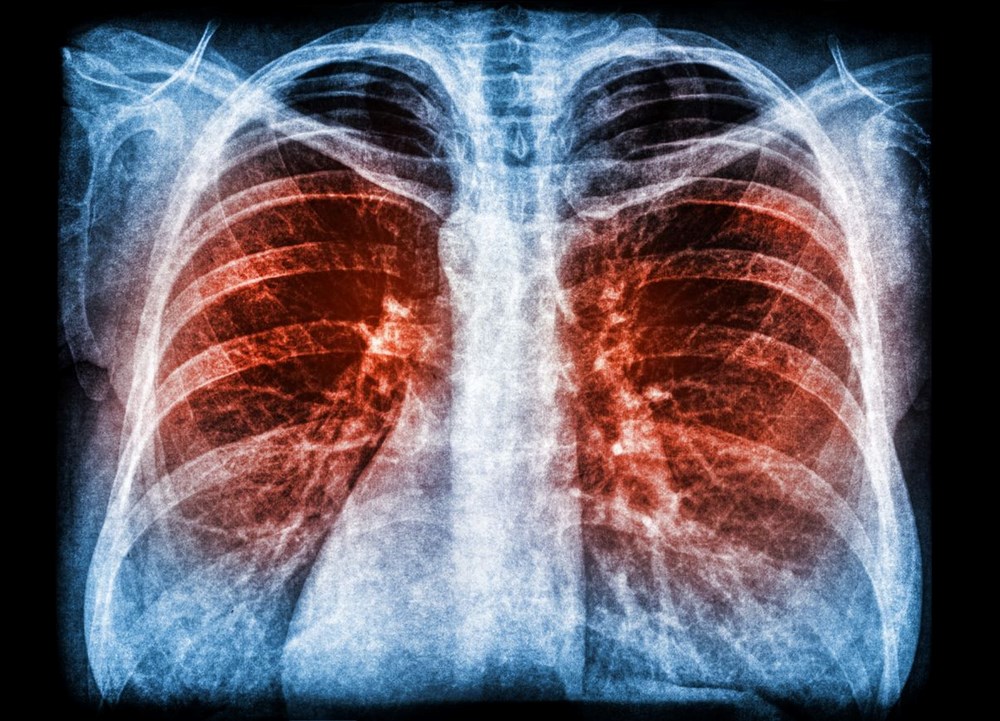

Kara Veba olarak da bilinen Kara Ölüm, insanlık tarihinde kaydedilen en ölümcül salgındır.

Kara Veba’nın Avrasya ve Kuzey Afrika’da yaklaşık 150 milyon kişinin hayatını kaybetmesine neden olduğu düşünülmektedir.

1347-1351 yılları arasında Avrupa’da zirveye ulaşan salgın, insanlık tarihinde kaydedilen en ölümcül salgındı. Hastalığın sebebi Yersinia pestis bakterisidir.

Kara Ölüm’ün kökeni tartışmalıdır. Daha önce yapılan araştırmalarda salgının ya Orta Asya’da ya da Doğu Asya’da ortaya çıktığı belirtilmişti.Kara Veba’nın ilk kesin görünümü 1347’de Kırım’da olduğu iddia edilirken, Kırım’dan, büyük olasılıkla Ceneviz gemilerinde seyahat eden ve siyah farelerde yaşayan pireler tarafında